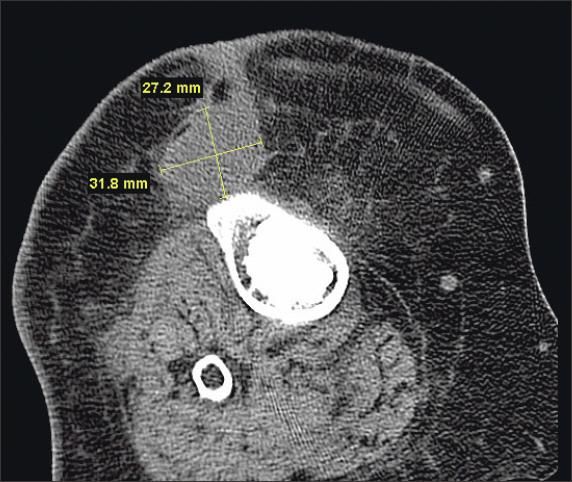

The patient's laboratory workup was remarkable for a C-reactive protein level of 16.68 mg/dL and an erythrocyte sedimentation rate of 31 mm/h. The white blood cell count and differential were normal. A CT scan of the right knee revealed a low density soft tissue mass anterior to the tibial tuberosity, with the bone at this level demonstrating mild irregularity (Figure 1). Triple-phase, technetium- 99m bone scanning showed intense delayed uptake in the right patella and tibia (Figure 2). The cellulitis was treated with vancomycin and nafcillin until culture results were negative for bacteria.

Figure 1 -

A CT scan of the right knee demonstrates a low-density soft tissue mass anterior to the tibial tuberosity. The bone demonstrates mild irregularity.